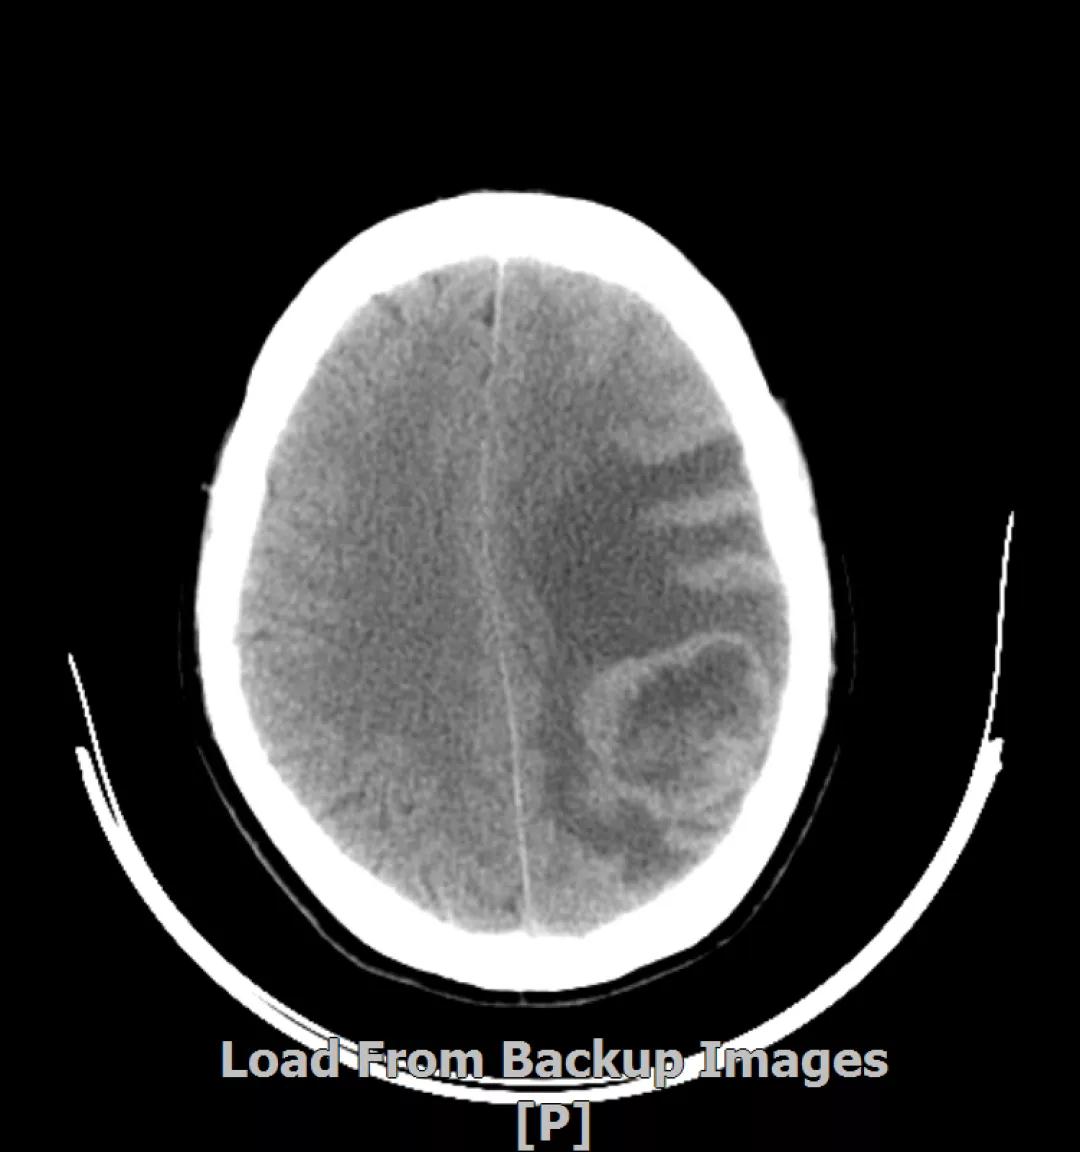

头颅增强MR:左侧顶颞叶见片状T1WI低信号、T2WI高信号影,病灶大部信号接近脑脊液,增强后术区边缘左侧顶叶见结节状强化影,大小约10x8x11mm,较2019-03- 15MR老片大致相仿;右侧脑室三角区见结节样T1WI等低信号、T2WI不均匀稍高信号影,增强后不均匀明显强化,大小约24x18x20mm,较2019-03-15MR老片明显增大;两侧半卵圆区、侧脑室旁见较对称片状T1WI低信号、T2WI高信号影,增强后未见明显强化,较前片相仿;余脑室、脑池、脑沟大小形态可,中线结构向左偏移。

左顶颞叶转移瘤治疗后改变

右侧脑室三角区旁强化结节,较2019-03-15MR老片明显增大 左侧顶叶强化结节,较2019-03-15MR老片大致相仿

两侧脑室旁云絮状异常信号,考虑放疗后改变